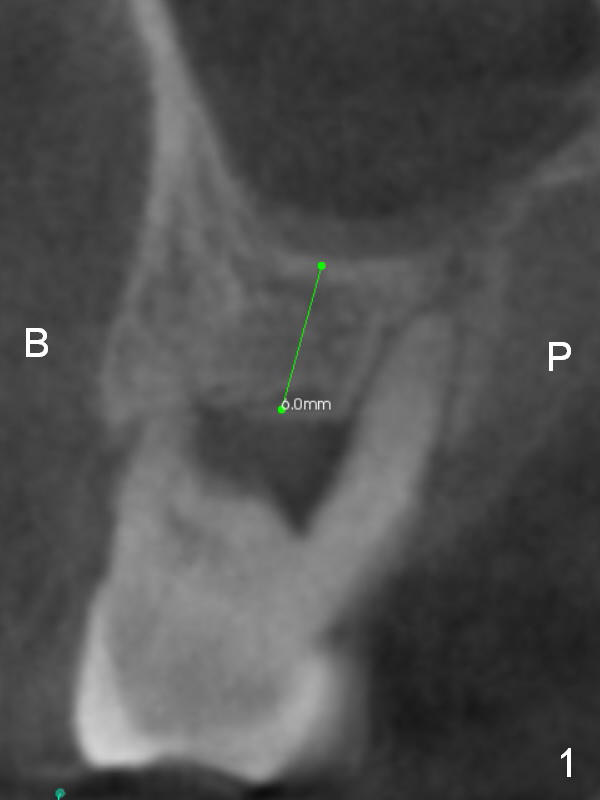

A 44-year-old man requests an implant at #3 because of mobility. It appears that the bone height decreases from 6 mm (Fig.1,2: 3 years ago) to 4 mm (Fig.3,4, recently). After extraction and Clindamycin treatment, take PVS impression of the socket. Use initial drill with drill stopper of 3 mm and round burs with stoppers from 4 to 5 mm. If the buccal (B) and palatal (P) plate defect is severe, use a regular implant. Otherwise use an extra wide one. The advantage of the latter is length as short as 6 mm vs. 8 mm for the regular one. For the latter, 2 mm of the implant will be in the sinus (Fig.4 red box), 4 mm in bone (pink box) and 2 mm in the socket (orange box; to be surrounded by bone graft). Since the gingiva is 6 mm (Fig.4 green box), an abutment with 6 mm cuff should be chosen. To reduce occlusal interference, select abutment height 4 mm.

Recently periodontal abscess occurs with purulent discharge from the buccal sulcus (Fig.5 *) and palatal gingiva erythema and edema (Fig.6 *). The buccal and palatal plates are most likely defective. A small diameter implant should be placed. The infection at #3 may be the cause of failure of implant at #31 (redo).